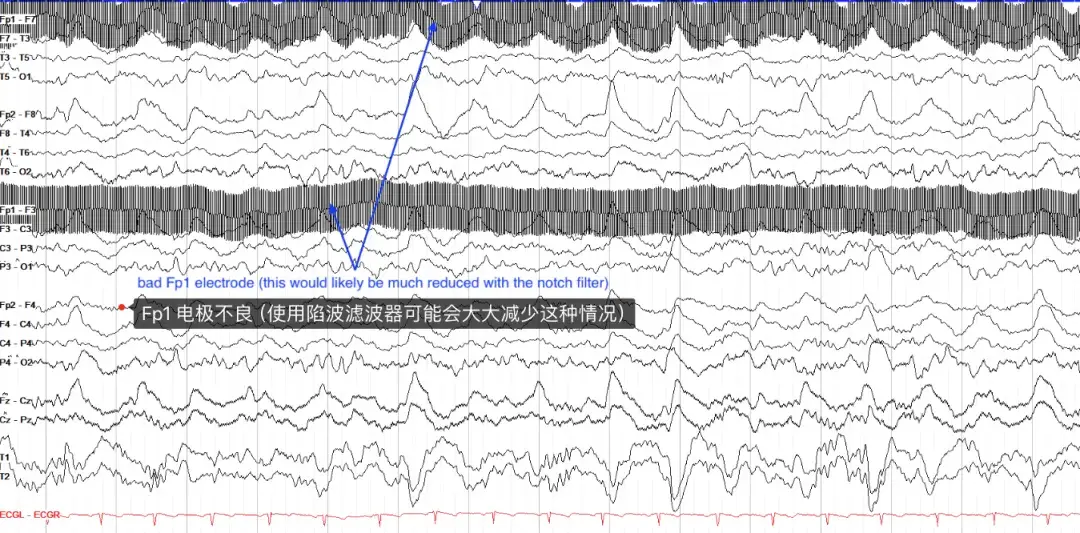

电伪影最常见的原因是通过电线传输的 60 Hz (如美国)电活动(某些地区为 50 Hz,如欧洲等)的干扰。当然,电伪影是一种非常快速、非常单调的活动,可以使用陷波滤波器选择性地去除 60Hz 的所有 EEG 活动(这不会影响对信号的解释,因为头皮 EEG 上没有大脑活动那么快)。在下面的示例中,陷波滤波器未打开,并且 Fp1 电极可能不太正确,导致大量电气干扰。

电极本身也会产生伪影,通常是在电极随着时间的推移而松动或被环境中的物体碰撞的情况下。